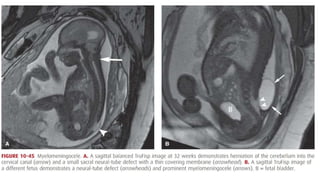

• 10.45

MAGNETIC RESONANCE IMAGING •The fetus was first studied with MR imaging in the mid-1980s, when image acquisition was slow and motion artifact was problematic • Since then, technological advances that allow fast-acquisition MR protocols have been developed • Image resolution with MR is often superior to that with sonography because it is not as hindered by bony interfaces • MR may be a useful adjunct to sonography in evaluating and further characterizing suspected fetal abnormalities.

Adjunct to FetalTherapy • As indications for fetal therapy have increased, MR imaging has been become more routinely used to outline abnormalities preoperatively • At some centers, before laser ablation of placental anastomoses for twin- twin transfusion syndrome, MR imaging is performed to assess the brain for IVH or periventricular leukomalacia • If fetal surgery is considered for sacrococcygeal teratomas, MR imaging may identify tumor extension into the fetal pelvis • The clinical importance of identifying women with placenta accreta

• #12 These newer protocols permit image acquisition in 1 second or less, which significantly reduces motion artifact and eliminates the need for sedation MR imaging, however, is not portable, it is time-consuming, and its use is generally limited to referral centers with expertise in fetal imaging. It may be helpful in the evaluation of complex abnormalities of the fetal CNS, thorax, gastrointestinal system, genitourinary system, and musculoskeletal system MR has also been used in the evaluation of maternal pelvic masses, placental invasion, and abnormalities of the pelvic floor and cervix The American College of Radiology and Society for Pediatric Radiology (2010) have developed a practice guideline for fetal MR imaging. This guideline acknowledges that sonography is the screening modality of choice. Moreover, it recommends that fetal MR imaging be used for problem solving to ideally contribute to prenatal diagnosis, counseling, treatment, and delivery planning Human studies and tissue studies support the safety of fetal MR imaging. Repetitive exposure of human lung fibroblasts to a static 1.5-T magnetic field has not been found to affect cellular proliferation Fetal heart rate patterns have been evaluated before and during MR imaging, with no significant differences observed (Vadeyar, 2000). Children exposed to MR as fetuses have not been found to have an increased incidence of disease or disability when tested at age 9 months or 3 years (Baker, 1994; Clements, 2000).